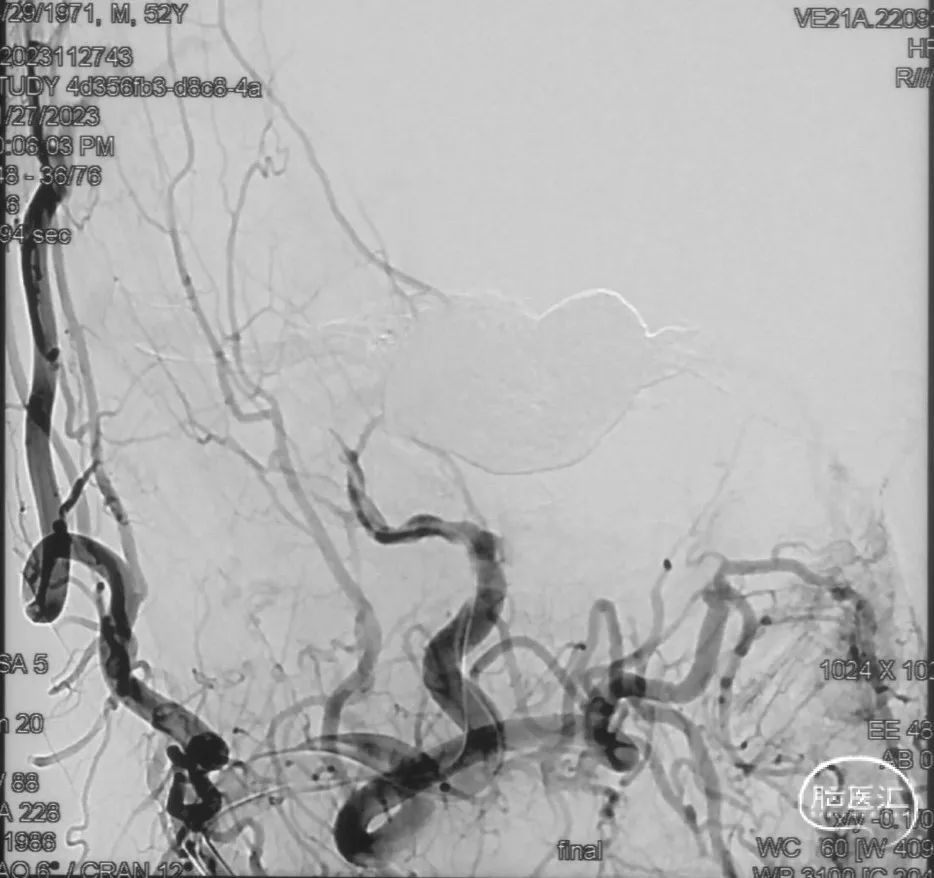

影像学的随访

术后9m

右侧颈内动脉造影未见瘘口显影及静脉早显

右侧颈外动脉造影未见瘘口显影及静脉早显

左侧椎动脉造影未见瘘口显影及静脉早显